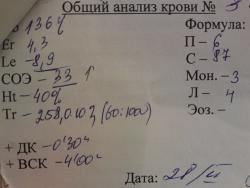

Ее ОАК от 28.02.11 (на момент поступления):

От 2.03.11

И от 03.03.11